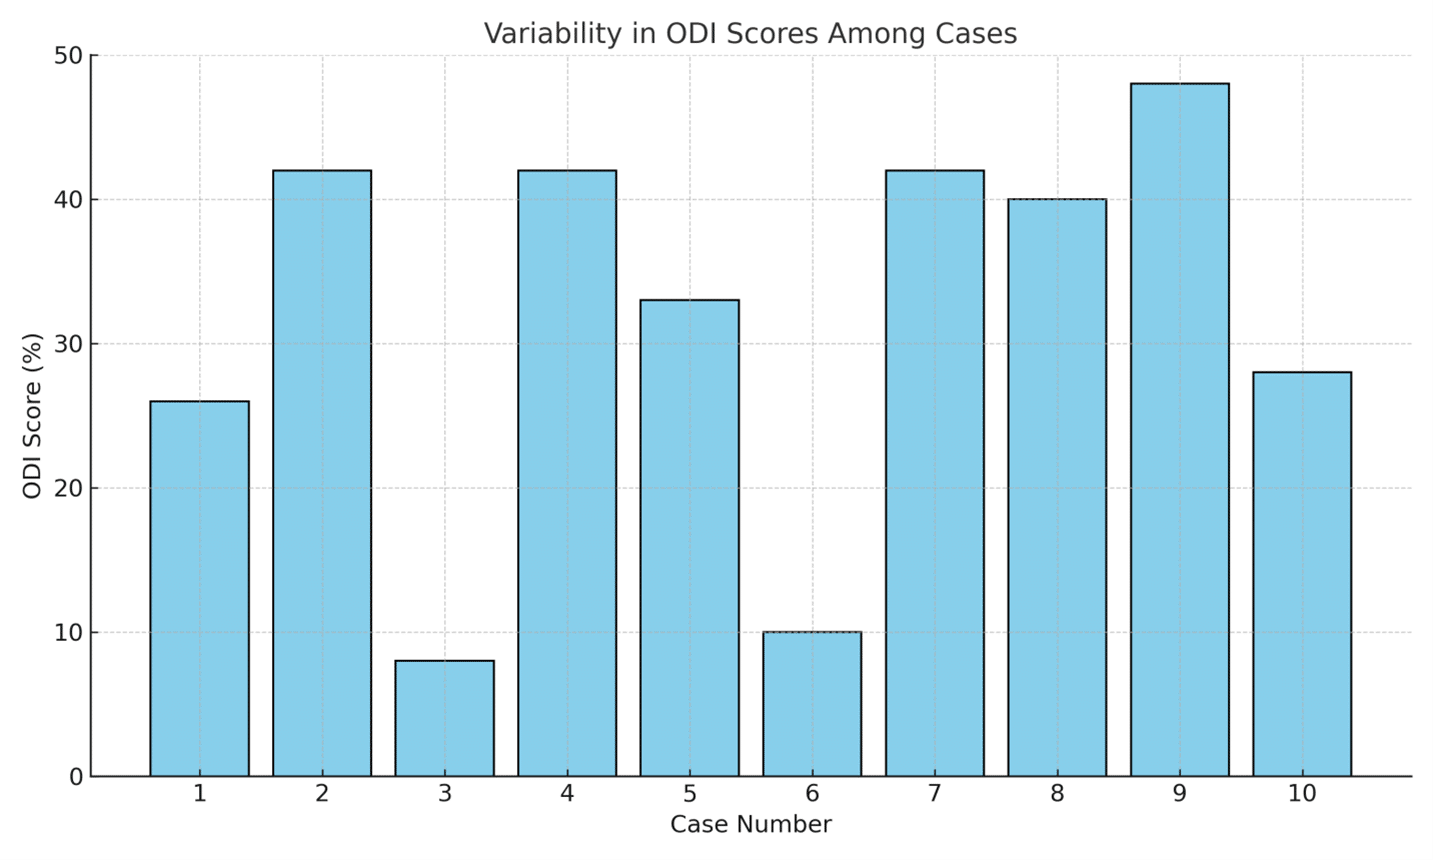

The Impact of Low Back Pain on Quality of Life of Women in Quetta, Balochistan

Background: Low back pain (LBP) is a prevalent condition that affects the quality of life (QOL) and daily functioning of...Read More